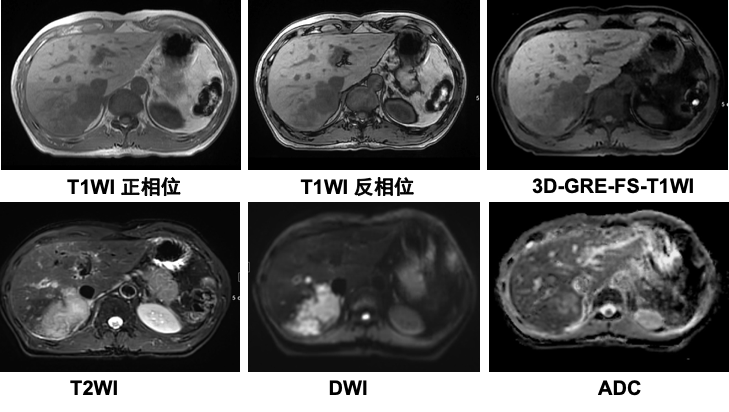

MixiMRI勉強会 脂肪抑制いろいろ 最近やっと勉強する気になったのですが、疑問が次から次へと出てきます。ここでは脂肪抑制についてお聞きしたいと思います。 脂肪抑制にもいろいろありますよね。 T2、PD、T1など。また、SE系、GRE系の違いもありま. ・骨盤部ではmriを,腹部ではctを第一選択にする. ・t1強調画像ではt1が長いほど磁化の回復が遅れるため信号が低く(黒く),t2強調画像ではt2 が長いほど磁化の減衰が遅れるため信号が高く(白く)描出される.t1とt2の組み合わせで組 t1強調画像はctの画像と似ており、脳の解剖学的な構造が見やすいという特徴があります。. 造影剤投与によりT1緩和時間が大きく短縮されますので基本的に脂肪抑制T1強調画像をベースに撮影が行われます。 ③実際の症例を提示します。 1) Stage I 腎細胞癌のdynamic MRI画像です。 左腎臓上極に1cm大の遷延性濃染する腫瘍を認めます。.

放射線技師向け kenminkei11. 2.MRIのパルスシーケンス 表在性軟部腫瘍では病変部位や形態が様々で あり,プロトコールを標準化しづらい.当院で 表在性軟部腫瘍の画像診断 391 図1石灰化上皮腫 (a)(b)(c)後背部正中の皮下腫瘤は,MRIのT1強調像,T2強調像でともに低信号で辺縁に. 肝細胞癌はt2強調画像、拡散強調画像で高信号、t 1 強調画像では低信号を呈している。造影ダイナミック検査早期相ではgd.

MRI ・T2強調像でのjunctional zone. 15分で分かる(?)MRI 古典力学的説明※1 MRI原理へのいざないPart 1 1個のプロトンから15分単位で理解できる(?) 基本的な信号強度 Part 1 プロトン密度、T1、T2と信号強度 ※学部学生は最低でもPart 1を理解すること. 4.mri:撮像法と画像所見 角谷 眞澄 藤永 康成 はじめに 肝疾患の診断にmriが期待されるのは,その優れた 組織コントラスト能によるところが大きい.t1強調像, t2強調像にて肝細胞性結節性病変は様々な信号強度を.

医学科普大讲堂 怎样区分不同序列的磁共振图像 看点快报

搞定这3 个问题 零基础也能读懂腹部mri 临床

这六大mri读片技巧 影像医生必须掌握 腹部医学影像论坛 二十次幂

搞定这3 个问题 零基础也能读懂腹部mri